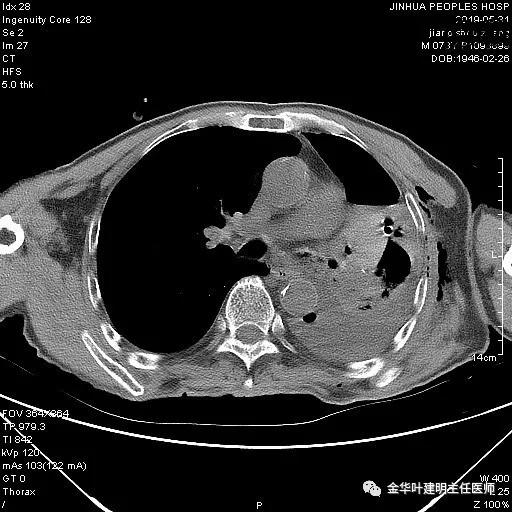

6.4上午:24小时引流出血性乳糜液1800毫升。是否再次手术进行右进胸胸导管结扎,抑或继续保守治疗非常纠结!压力非常大!!多方讨论会诊无法取得一致意见,但一般认为,引流量在1000毫升以上宜积极手术。情况与浙二医院范军强教授联系,请求指导,范教授认为左侧肺手术,损伤胸导管主干的机会较小,多数可保守治疗而愈。在他们的病例中,也有结扎胸导管后引流量仍无减少,效果并不能完全保证。建议可以考虑胸管夹管观察(因为淋巴管压力低,予以适当的压力,漏出量可能会明显减少),同时继续禁食,并静脉营养支持,引流管口可能会有渗液,注意更换敷料。与家属充分沟通后决定试夹管;这天血色素9.0 g/L;胸部CT复查示: